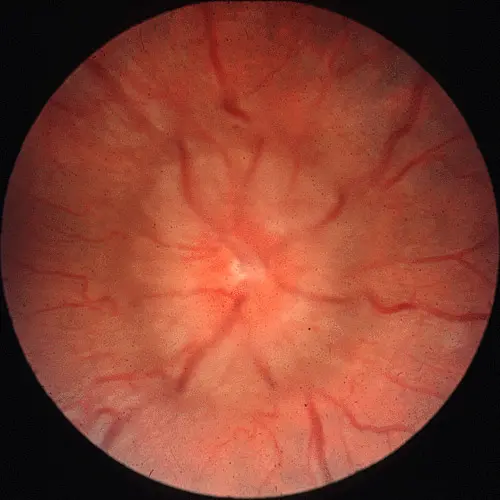

Optic Disc Swelling

Optic Disc Swelling: Needs diagnosis based on cause.

Differentiating Causes: Check if Unilateral or Bilateral & check Vision.

If Bilateral Swelling + Normal Vision (Early):

- Likely Papilledema (due to ↑ Intracranial Pressure).

- Usually no pain with eye movement.

- Look for headache, nausea. Needs neuro-imaging.

If Unilateral Swelling (or Normal Disc) + Acute Vision Loss + Pain with Eye Movement:

- Likely Optic Neuritis (Inflammation).

- Vision affected early and significantly. Color vision often poor.

- Needs investigation (e.g., MRI) for causes like MS.

Difference:

- Papilledema = Pressure problem, typically bilateral, vision okay initially.

- Optic Neuritis = Inflammation problem, typically unilateral, vision poor early, often painful eye movement.